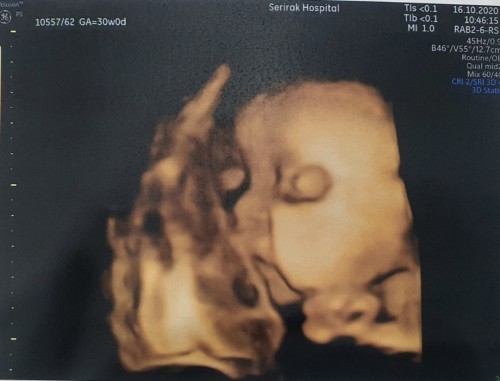

30+3 เพศชายจ้า